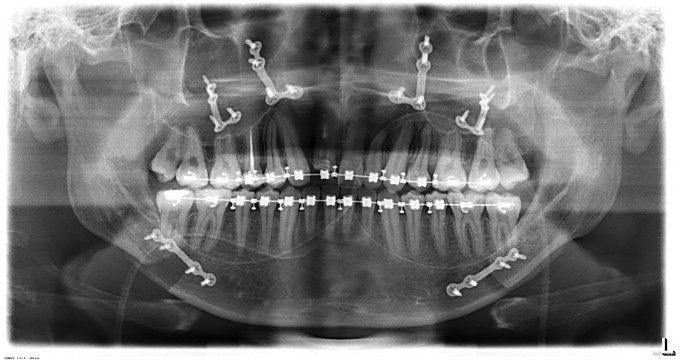

自觉上颌后缩 ,下颌前突数年。

面部发育良好,中线左右对称,上中下比例协调,面下三分一过长前突,颏顶点正中。左侧颞下颌关节无弹响无疼痛动度正常,右侧颞下颌关节开口末期可触及绞索感,无弹响无疼痛动度正常。张口度5.5cm,开口型正常。上下牙弓关系不协调,前牙反牙合后牙近中错牙合,龋齿无,牙周病无。

诊断:1.上颌后缩2.下颌前突,全麻下行上颌LeFortⅠ型截骨前徙术+双侧上颌骨骨内坚固内固定术+双侧下颌骨矢状劈开后退术+去骨皮质术+坚固内固定术+双侧邻近瓣转移修复术。